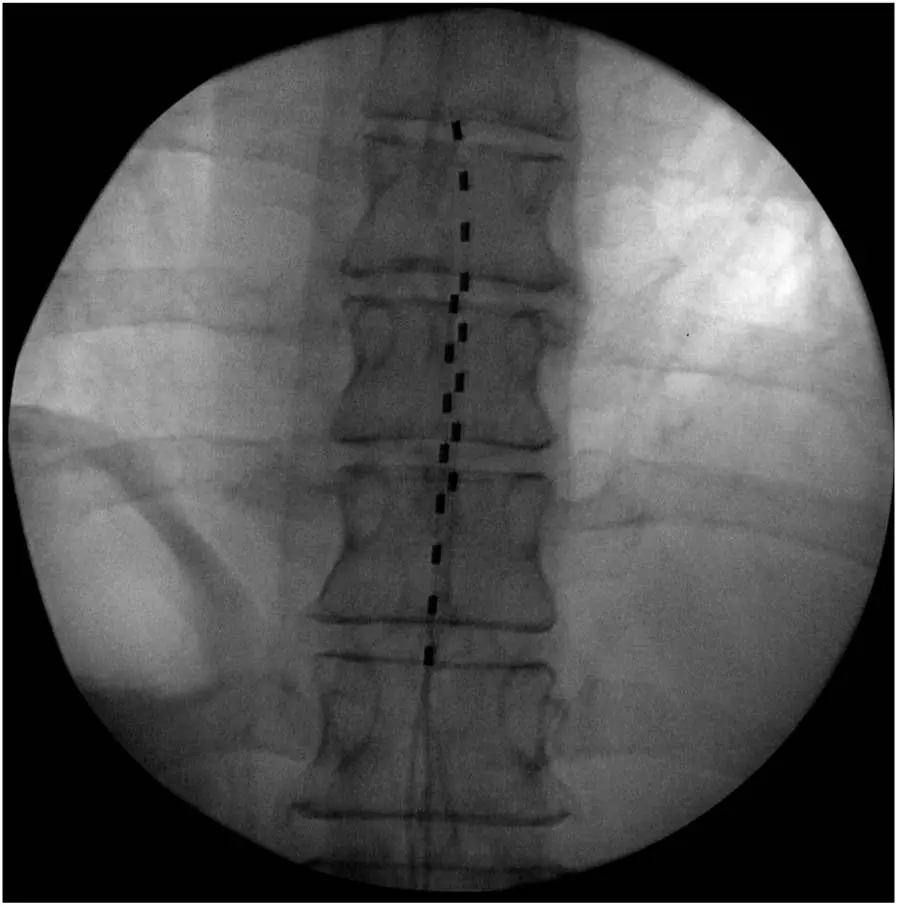

如果患者在试验期内对脊髓电刺激反应良好,且医生认为长期治疗可能对患者有益,那么就会考虑进行永久植入手术。在手术前,医生会与患者充分沟通,讨论植入的具体方式、预期的治疗效果以及可能存在的风险等。手术过程中,患者通常会接受全身麻醉或局部麻醉,医生会在透视引导下,将永久性电极精准地植入到硬膜外间隙,并确保电极与脊髓的位置关系合适。电极植入后,会将其与植入式脉冲发生器(IPG)相连,IPG 通常会被放置在患者的腹部或臀部皮下。手术后,医生会对 IPG 进行编程,根据患者的个体情况设置合适的刺激参数,以达到最佳的治疗效果。